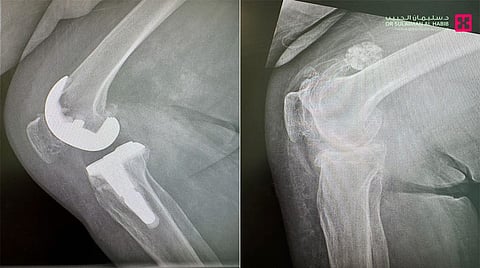

وقال د. محمد سكيك استشاري جراحة العظام والمفاصل، رئيس الفريق الطبي المعالج، أن المرأة راجعت المستشفى وهي على كرسي متحرك، وتشكو من طيف متنوع من الأعراض الحادة، أبرزها عدم القدرة على الحركة والنوم بسبب الآلام الحادة وانتفاخ المفصل وتقوس بالساق، وأجريت لها عدة فحوصات كالتصوير بالأشعة السينية، وبينت النتائج وجود خشونة حادة في مفصل الركبة وتآكل بالغضاريف.

وأضاف د. سكيك الحاصل على الزمالة البريطانية والكندية، أن المراجعة أجريت لها عملية متقدمة، باستخدام تقنية الربوت الجراحي، بدأت بتزويد النظام بالمعلومات الخاصة بها، بالإضافة إلى قياسات مفصل الركبة، وتفاصيل مفصل الركبة الصناعي المراد زرعه، وهي إجراءات تمنح الحالة في النهاية نتائج تعافي عالية الدقة، بما يتناسب مع بنية الركبة والأنسجة المحيطة بها، وأجريت العملية تحت التخدير النصفي، وتم فيها تصحيح التقوس الحاد باستخدام دعامة لتعويض تصلب وضعف الأربطة، ومن ثم استبدال مفصل الركبة بآخر صناعي نوعي، مناسب للحالة. استغرقت العملية نحو "90" دقيقة، وتكللت ولله الحمد بالنجاح التام، وتمكنت المراجعة من المشي بعد "3" ساعات من العملية، وغادرت المستشفى بعد "4" أيام، وهي بحالة صحية جيدة، وبذلك تخلصت من كافة الأعراض التي عانت منها طوال السنوات الماضية.